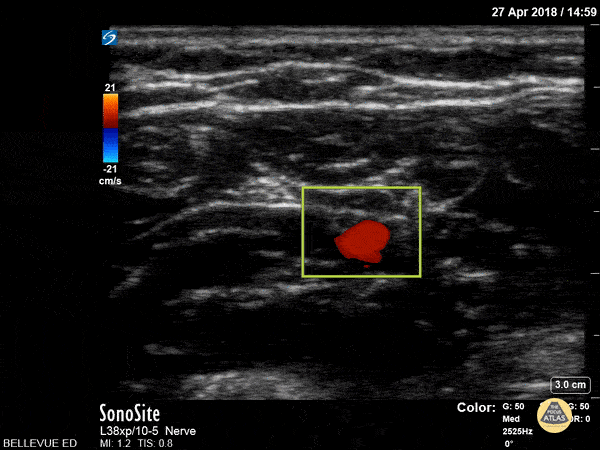

The ulnar artery with color doppler showing pulsatile flow, and the bright hyperechoic ulnar nerve visible to the left of the screen. Remember, the ulnar nerve is always “ulnar” to the ulnar artery. Hannah Kopinksi and Dr. Lindsay Davis - NYU Emergency Medicine